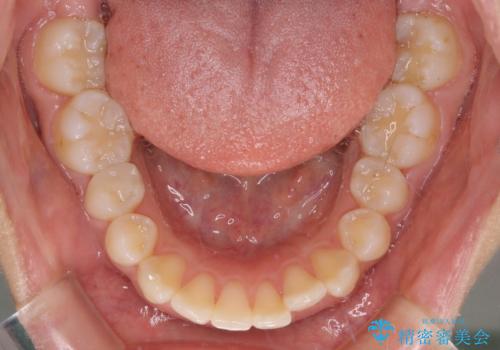

- 出っ歯で唇が閉じにくいとのことで来院された患者様です。

顎先に力を入れないと唇が閉じきれない口元であったので、上下左右の第一小臼歯4本を抜歯して、ワイヤー装置にて矯正治療を行うこととしました。

費用を抑えるため、金属の装置を選択されました。